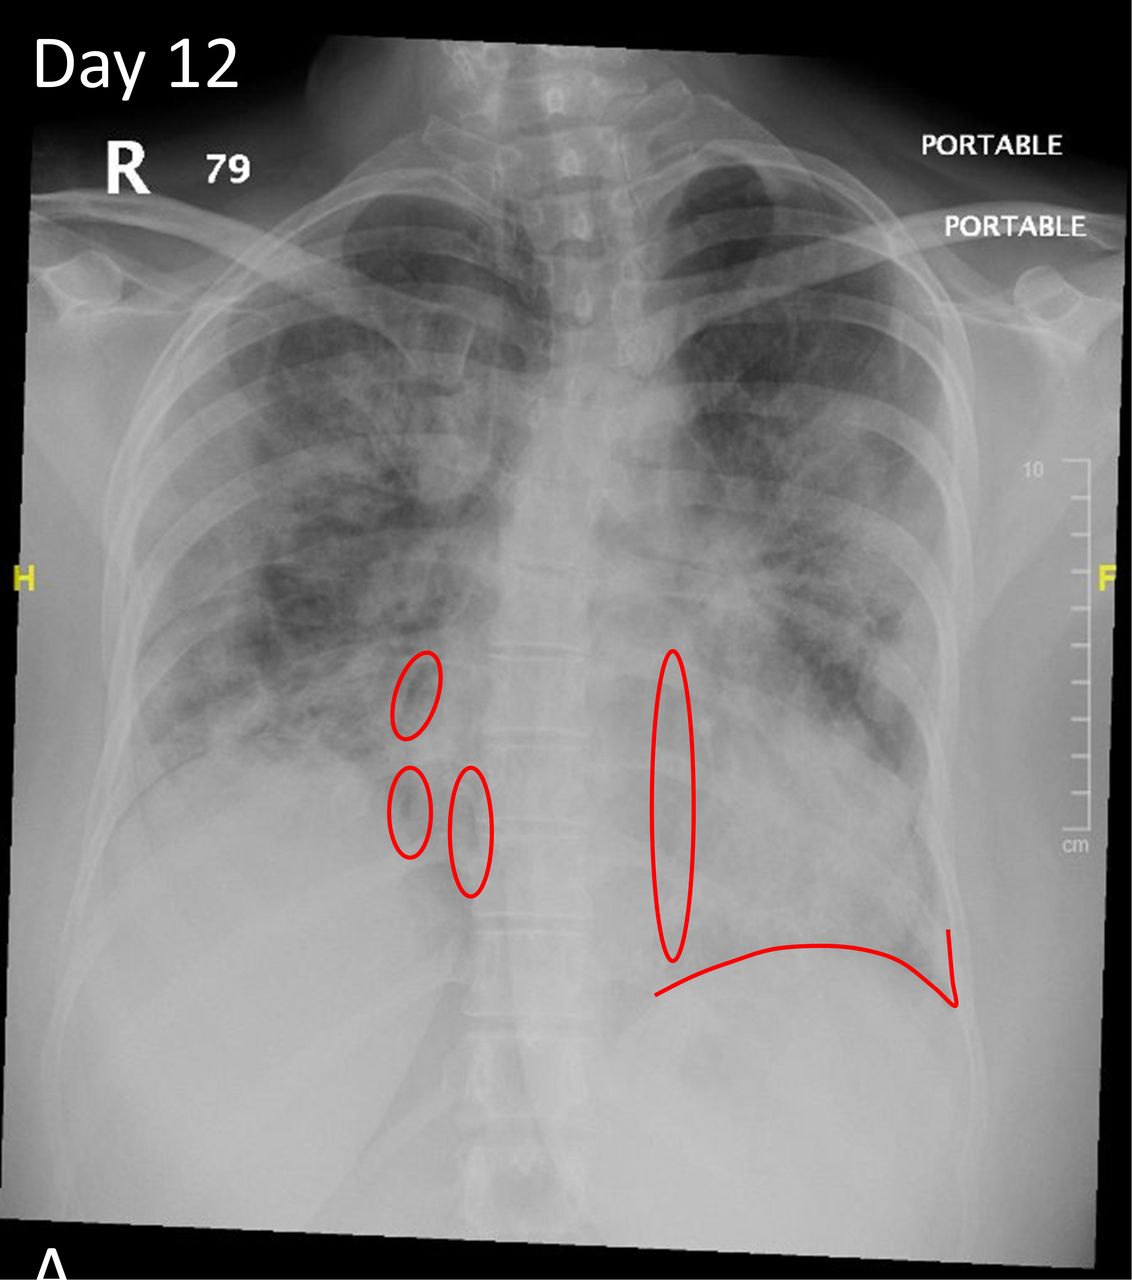

W zapaleniu płuc na zdjęciu RTG nacieki różnią się od raka czy obrzęku serca dynamiką – powtarzane zdjęcia po 24-48 godzinach pokazują ewolucję, np. zanik konsolidacji po antybiotyku w 70% przypadków bakteryjnych (dane z Polish Journal of Radiology, 2021). Interstycjalne zapalenie płuc cechują drobne, siateczkowate zacienienia rozlane obustronnie, w czasie gdy lobarne – ostre granice z granicą anatomiczną płata. Radiolog interpretuje „zagadki” jak znak sylwetki pnia oskrzelowego („drzewo oskrzelowe”) czy air bronchogram – powietrzne oskrzela w zacienionym tle, typowe dla konsolidacji. Effuzja opłucnowa towarzyszy w 30% przypadków, tworząc zacienienie w zatokie żebrowo-przeponowej.

- Połączenie z effuzją: w 25-35% ciężkich przypadków, wymaga USG do różnicowania.

Co oznacza „bilateralne zacienienia” w diagnozie? Wskazuje na obustronne zapalenie, np. wirusowe, z ryzykiem ARDS w 15% przypadków.

Wirusowe postacie zapalenia płuc na zdjęciach rentgenowskich klatki piersiowej często przypominają obrzęk płucny, z perihilarnymi smugami i zagęszczeniami w dolnych polach. Bakteryjne zapalenie płuc wykazuje z kolei szybką ewolucję – konsolidacja może ustąpić po 48-72 godzinach antybiotykoterapii, co potwierdza RTG kontrolne. Frazy takie jak charakterystyczne cechy bakteryjnego zapalenia płuc w rentgenie pomagają radiologom w szybkim różnicowaniu.